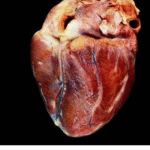

Per praticità, di seguito è possibile confrontare l’aspetto di un “Cuore Normale” e quello di un “Cuore dopo assunzione di Stupefacenti”: la differenza è macroscopica e palese, il cuore subisce una trasformazione delle sue fibre contrattili che si atrofizzano e induriscono, risultando meno efficaci e meno elastiche, rendendo il muscolo cardiaco asfittico e ancora meno efficiente a pompare tutto il sangue necessario, fino allo sfiancamento, tecnicamente la cardiomiopatia dilatativa.

La morte per cardiomiopatia dilatativa avviene a seguito di aritmie ventricolari mortali, edema polmonare acuto, con arresto cardiaco o respiratorio, e questa è probabilmente ciò che è successo alla Pop Star.